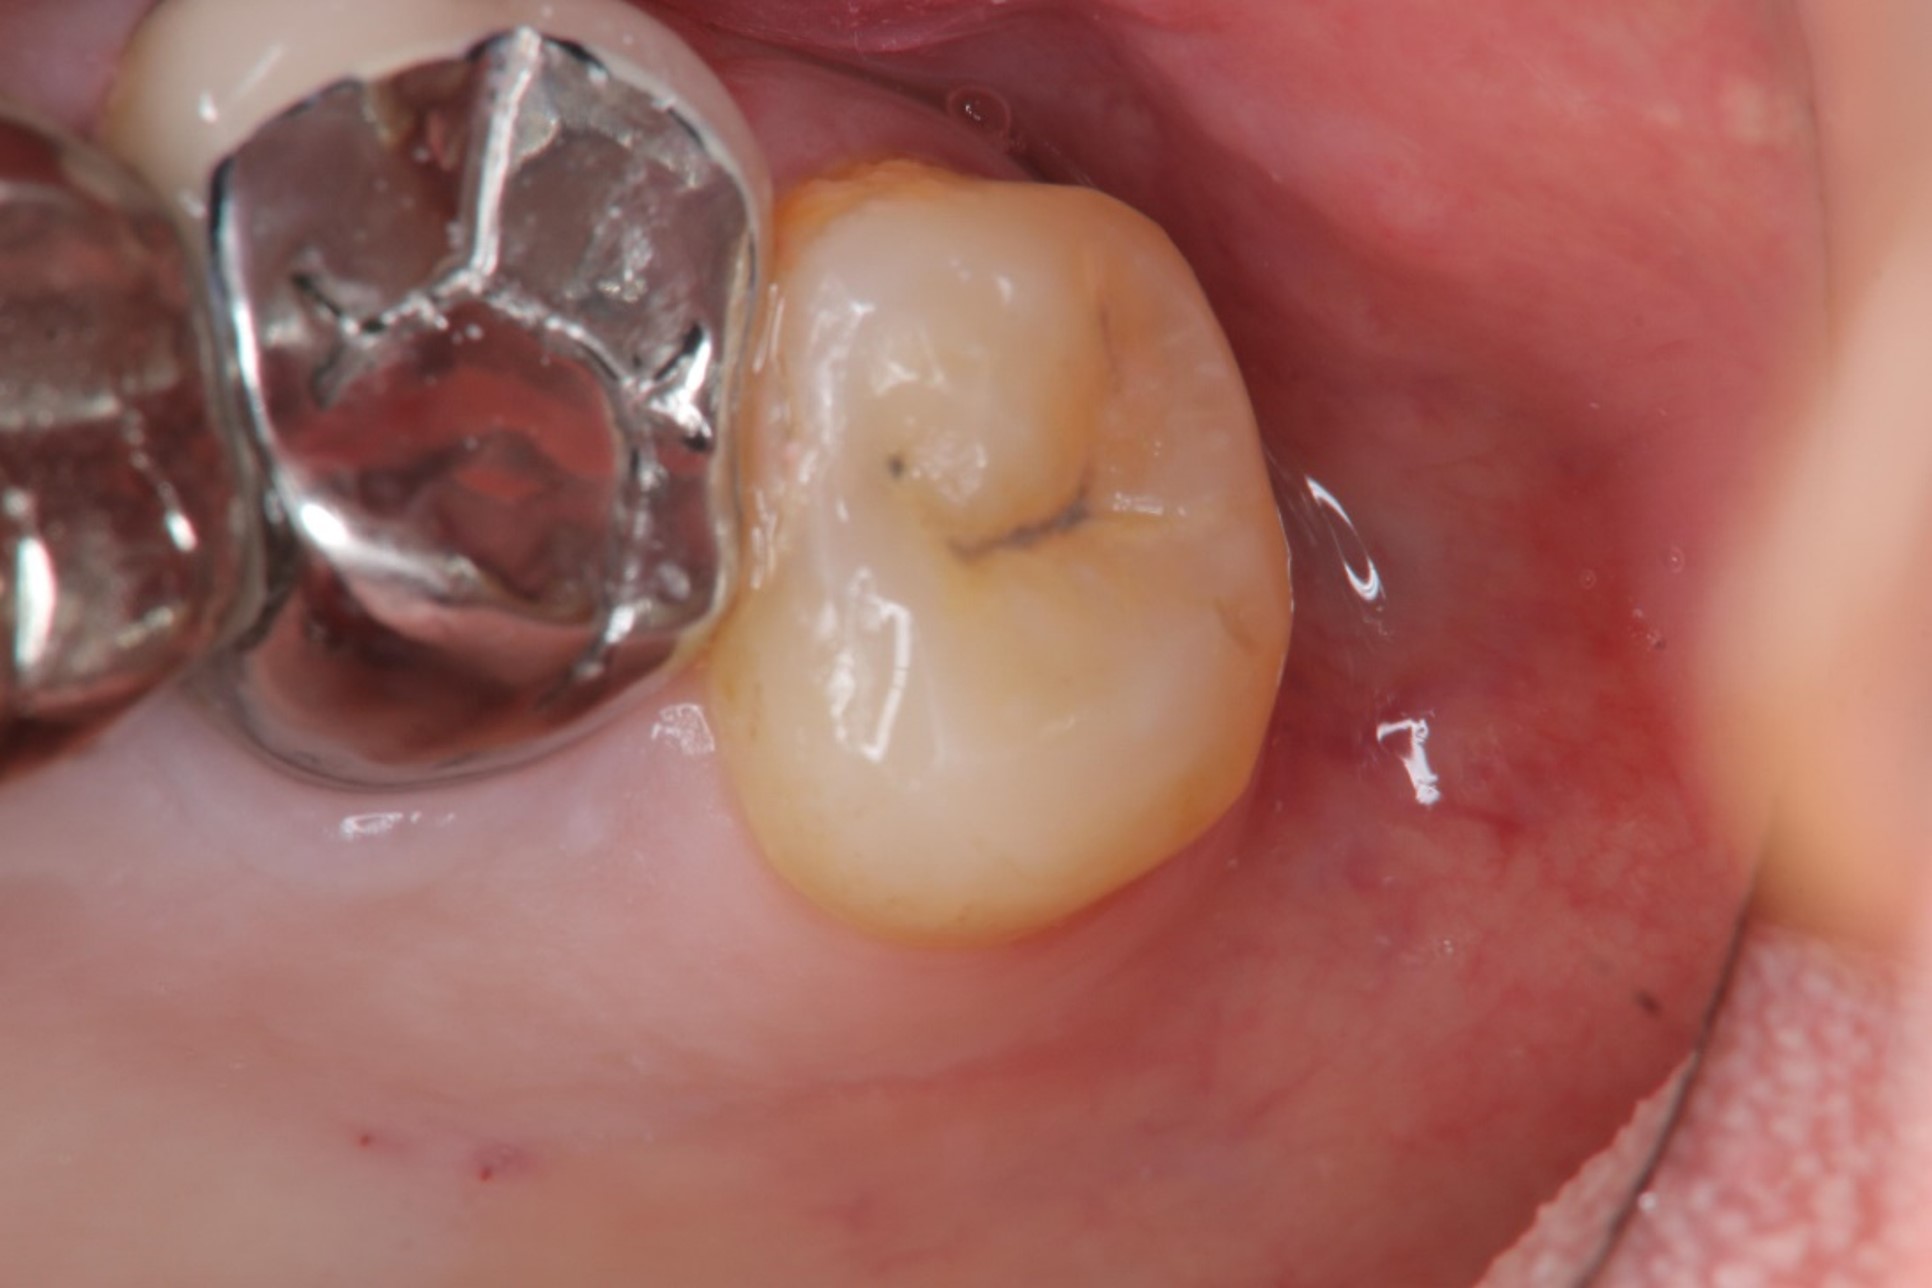

治療前,左上阻生齒深度蛀牙